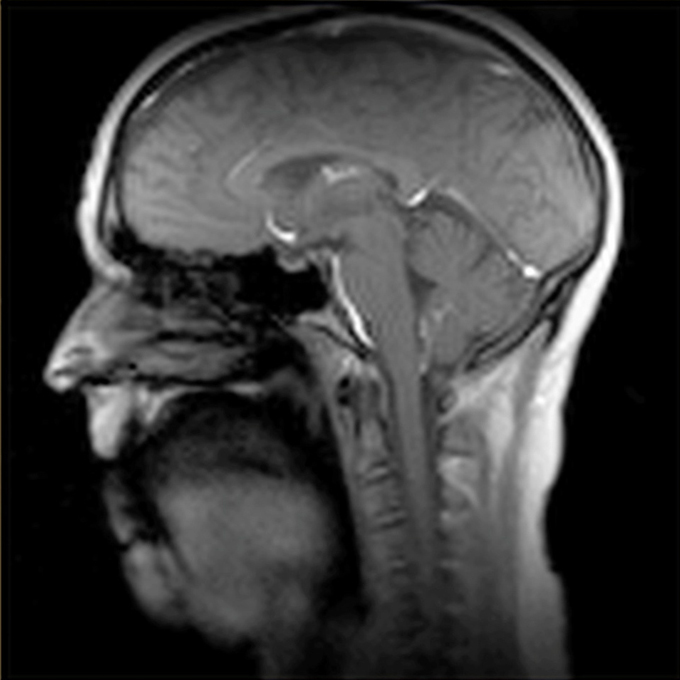

Professor Zhi-Pei Liang has helped develop a magnetic resonance imaging (MRI) technique that allows for viewing dynamic images of vocal movement at 100 frames per second - a speed far more advanced than any other in the world.

Thanks to the magnetic resonance imaging (MRI) capabilities in Beckman’s Biomedical Imaging Center, Johnson can view dynamic images of vocal movement at 100 frames per second — a speed that is far more advanced than any other MRI technique in the world.

“Typically, MRI is able to acquire maybe 10 frames per second or so, but we are able to scan 100 frames per second, without sacrificing the quality of the images,” Sutton said.

The dynamic imaging is especially useful in studying how rapidly the tongue is moving, along with other muscles in the head and neck used during speech and singing.

“In order to capture the articulation movements, 100 frames per second is necessary, and that is what makes this technique incredible,” Johnson said.